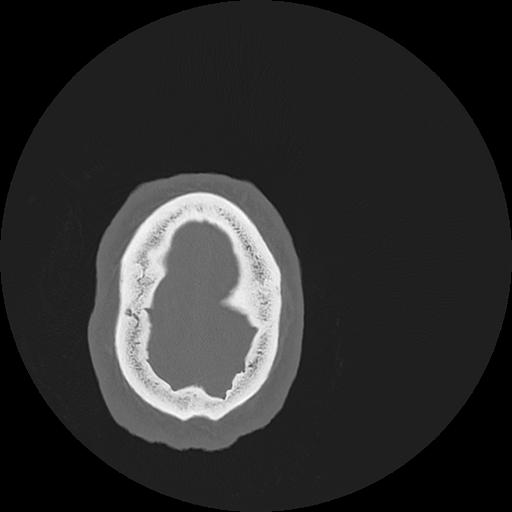

7 HUESO,,Vol,0.5,HUESO,,